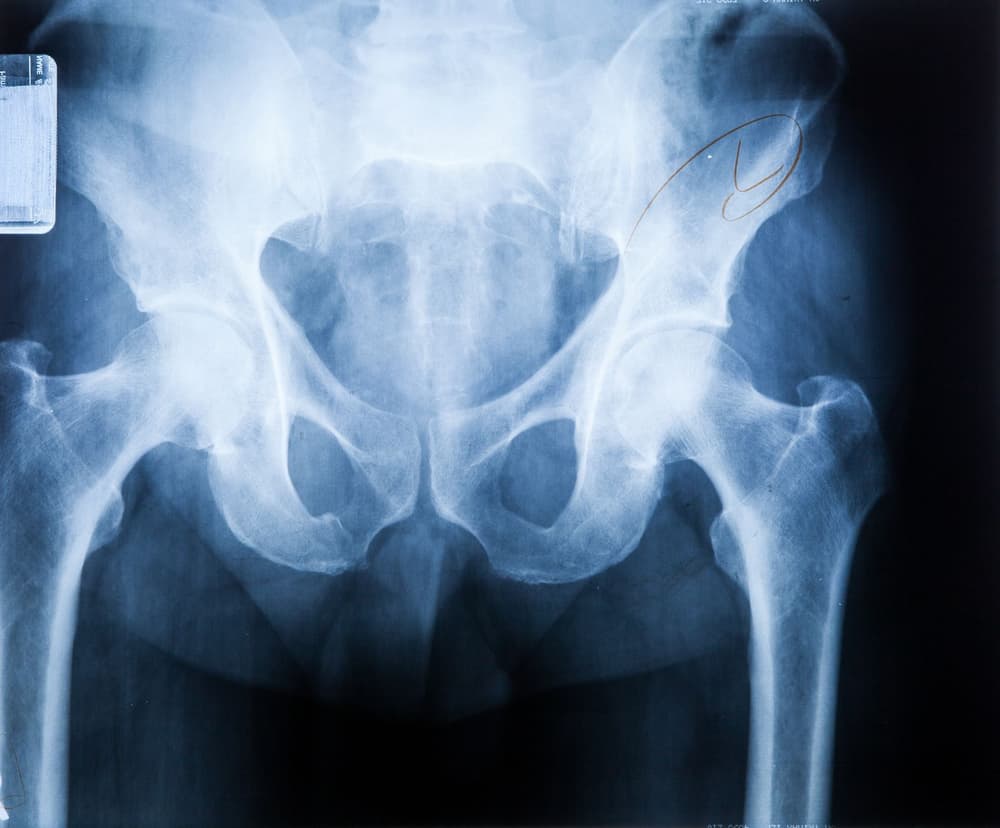

Zwichnięcie stawu biodrowego jest uszkodzeniem, w którym dochodzi do chwilowej bądź trwałej utraty kontaktu powierzchni stawowych ze sobą lub przemieszczenia kości w torebce stawowej – głowa kości udowej utraci kontakt z panewką w stawie biodrowym. Przyczyna jest zazwyczaj bardzo ciężki uraz.